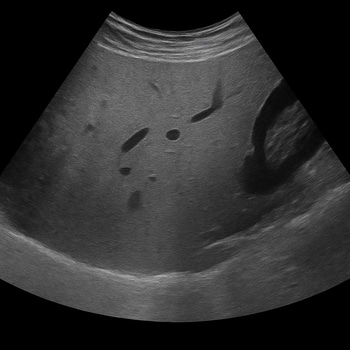

Ultrasound – The quick first-line method

Ultrasound is often the first step because it is highly accessible. It provides a quick visual overview of the liver and other abdominal organs.

Limitations: The method is sensitive to body composition; in cases of significant abdominal obesity, it can be difficult for sound waves to penetrate, leading to uncertain results.